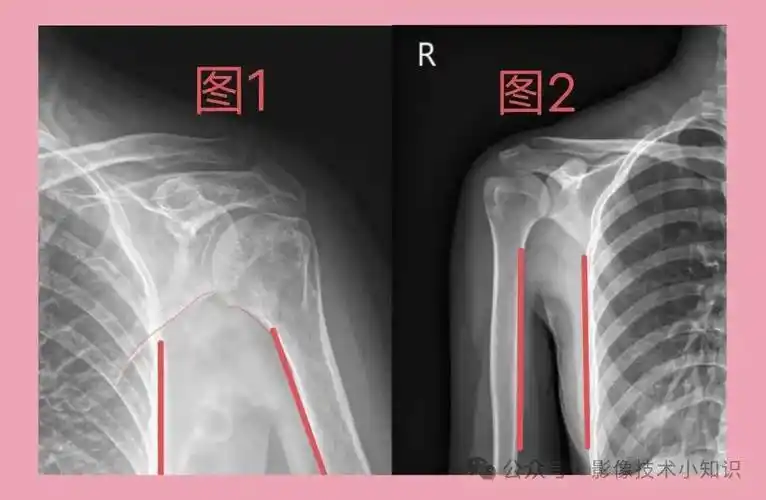

肩关节内收和外展, 对影像诊断的影响